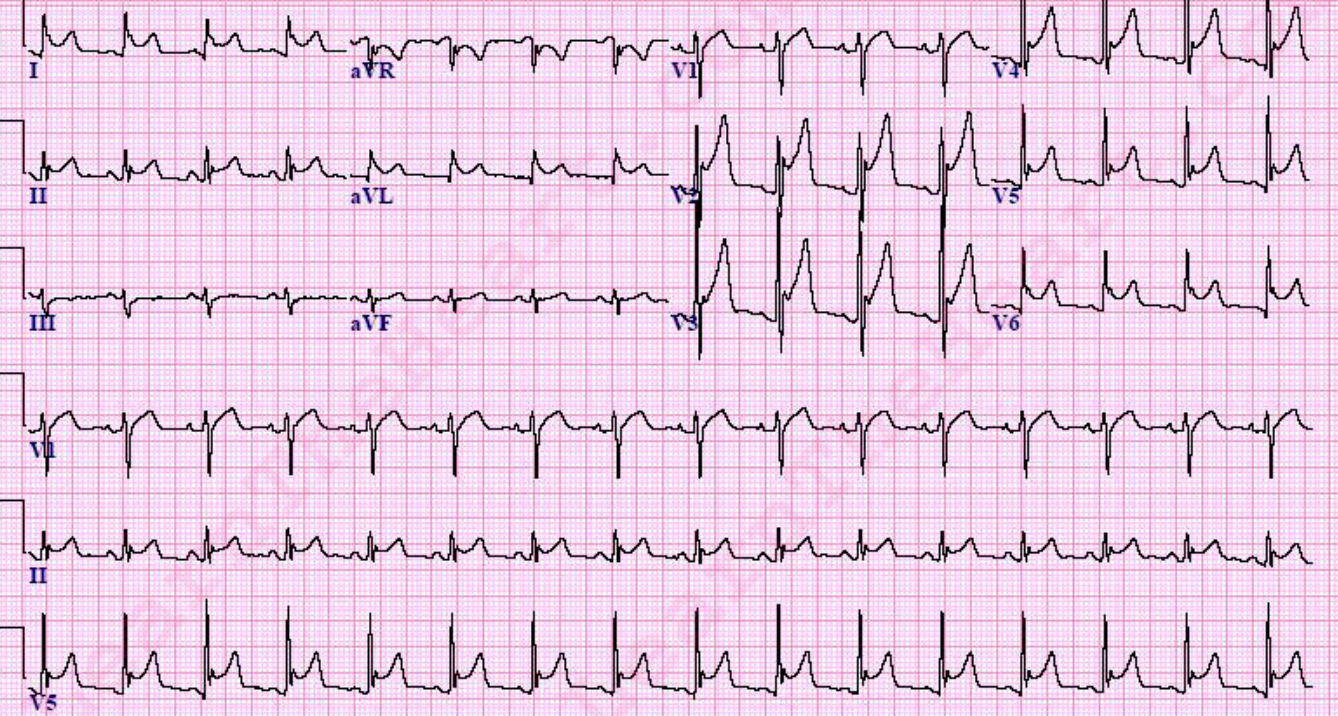

Case 6 Z

-

Describe the abnormal ECG finding?

p wave absent, irregular rhythm -

What is the diagnosis?

Atrial fibrillation

ECG of a man who has chest pain after 5 min of staircase climbing 1. abnormalities? a. Brady cardia (62-65 bpm) b. Prolonged PR interval (7 small squares)

2. Diagnosis? a. NSTEMI b. With Heart block first degree

3.2 further tests? a. Stress test b. Angiography c. echocardiography